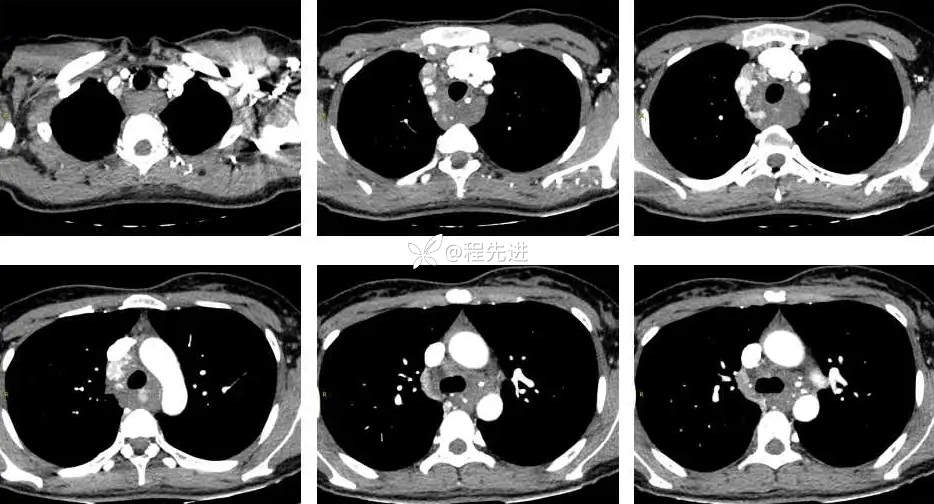

CT平扫+增强: